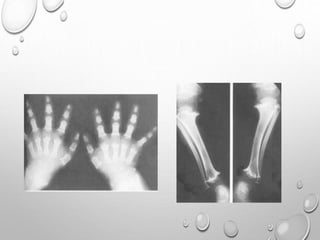

LIMBS

UL> LL

RHIZOMELIC TYPE

METAPHYSIS …..SPLAYING , CUPPING

GENU VERUM

TRIDENT HAND

TIBIA , ULNA ARE MORE SHORTENED THAN FIBULA , RADIUS

V SHAPED NOTCH IN GROWTH PLATE

SHORT , TUBULAR LONG BONES OF HAND AND FEET

FINGERS ARE OF SAME LENGTH